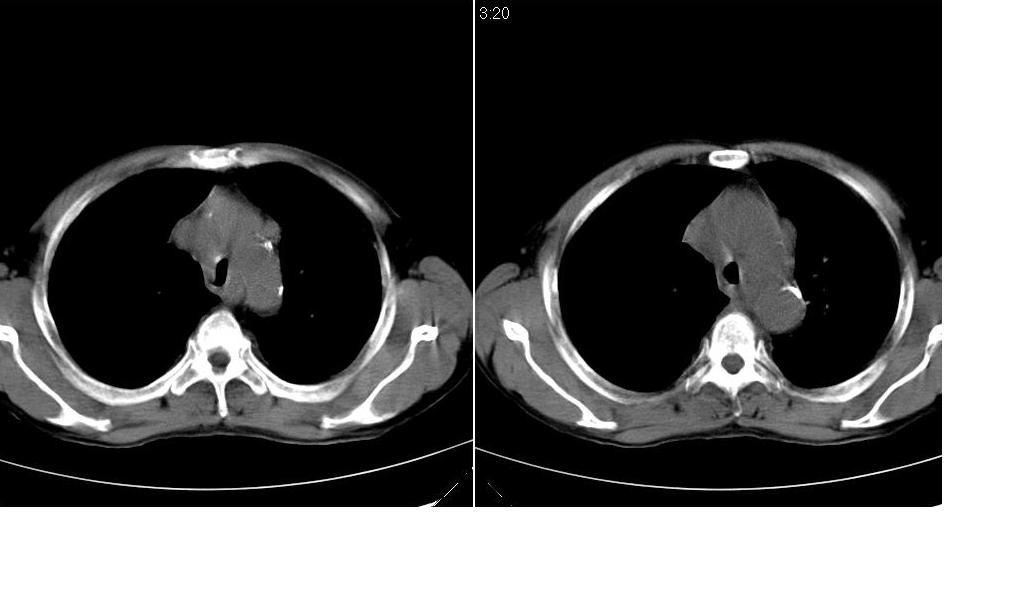

标题: CT10843:男 61岁,胸部CT平扫 [打印本页]

标题: CT10843:男 61岁,胸部CT平扫

男 61岁,已确诊肺癌半年余.

右肺小细胞肺癌并纵隔淋巴结转移。胸腔积液,心包少量积液。左肺改变不除外癌性淋巴管炎

考虑:1、右肺下叶中心型肺癌并纵隔淋巴结转移。胸腔积液。

2、心包少量积液。

考虑:1、右肺下叶中心型肺癌并纵隔及左肺门淋巴结转移。胸腔积液。

3、左肺改变与左肺门肿大淋巴结影压迫主支气管有关。